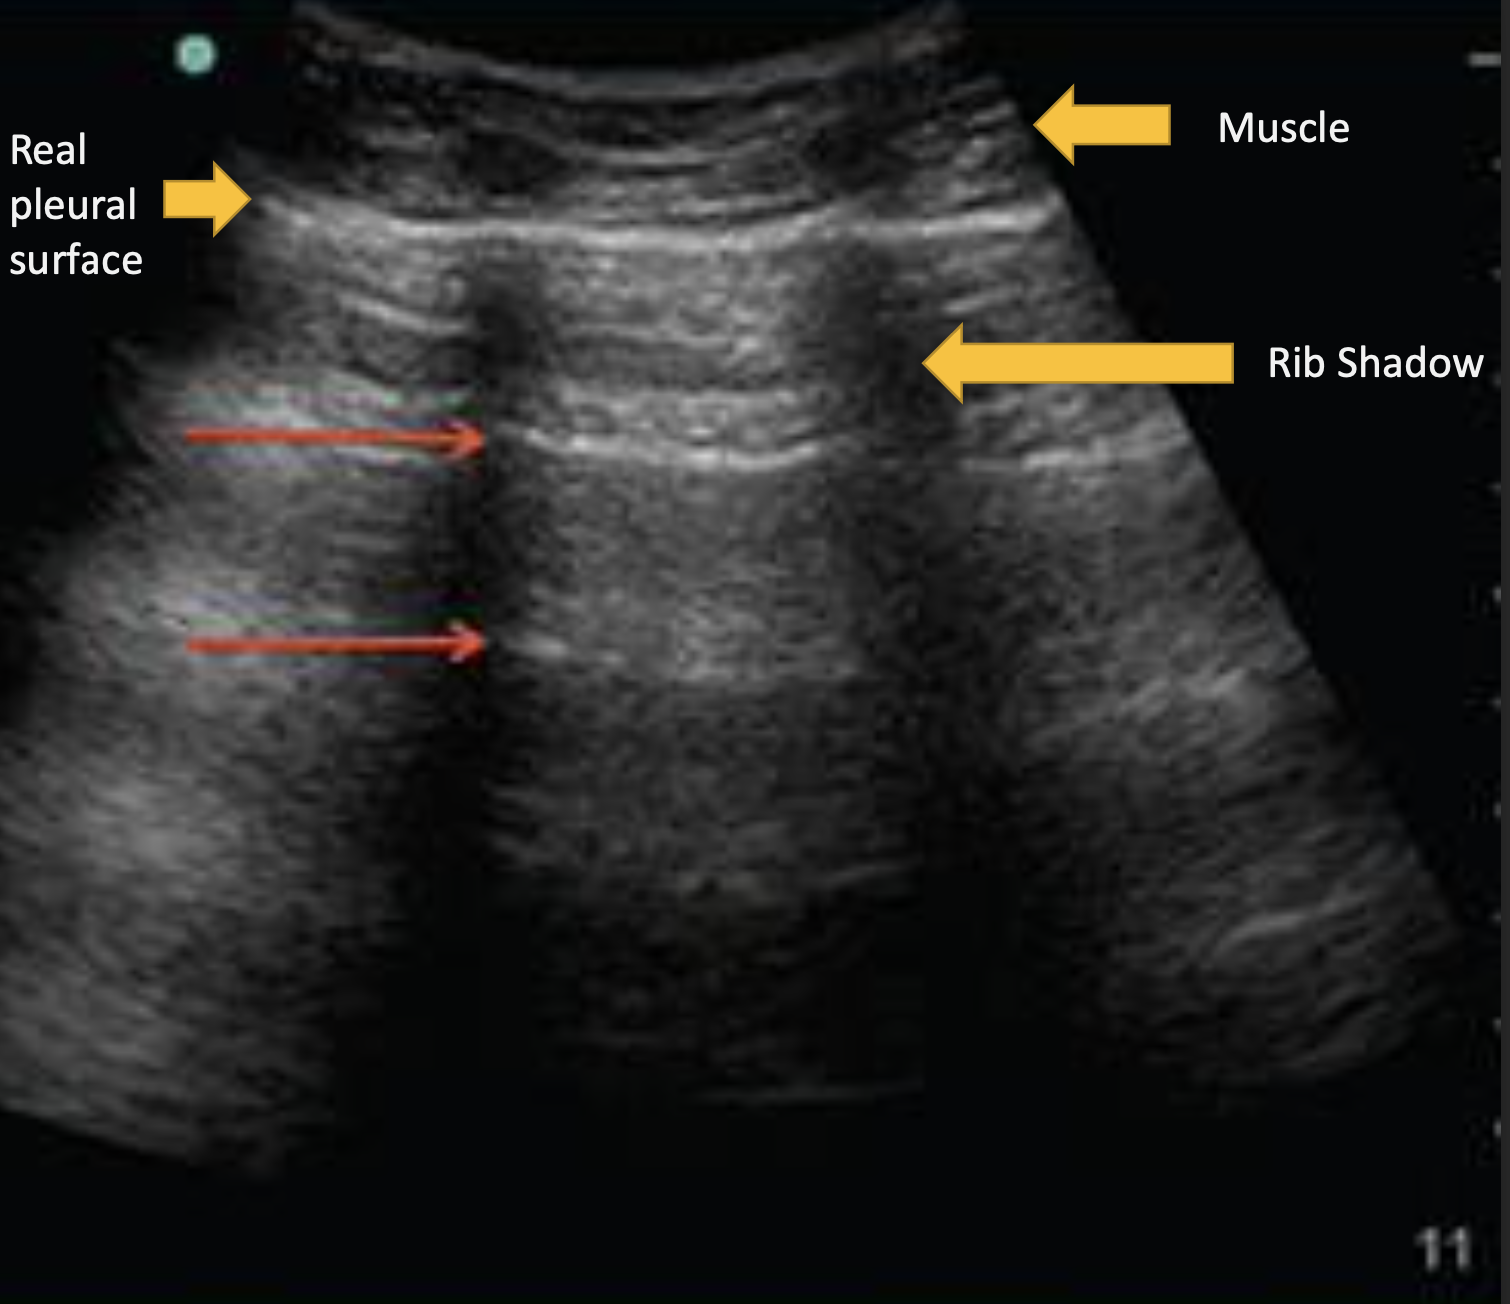

What ultrasound artifact cannot be seen below a structure so reflects back ALL waves?

Acoustic Shadow

ex. ribs